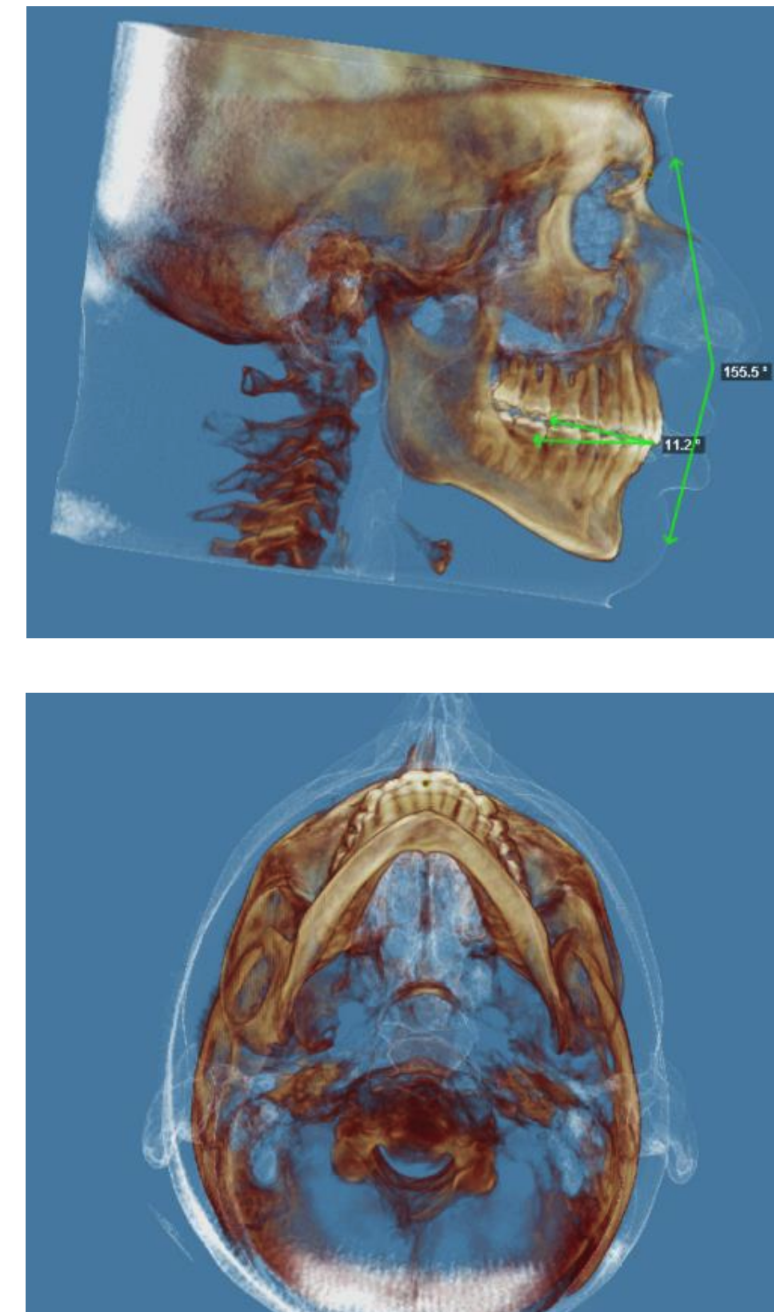

They are planning on doing a segmental 3-piece Lefort 1 which should give me about 5mm of expansion and 8mm of advancement, along with a CCW rotation of a few degrees (my dumbass forgot to ask how many) and a BSSO mandibular advancement of 12mm.

Feel free to ask any questions, also if any autists out there want to make comments about my scans, current appearance and my surgery plans then please do so.